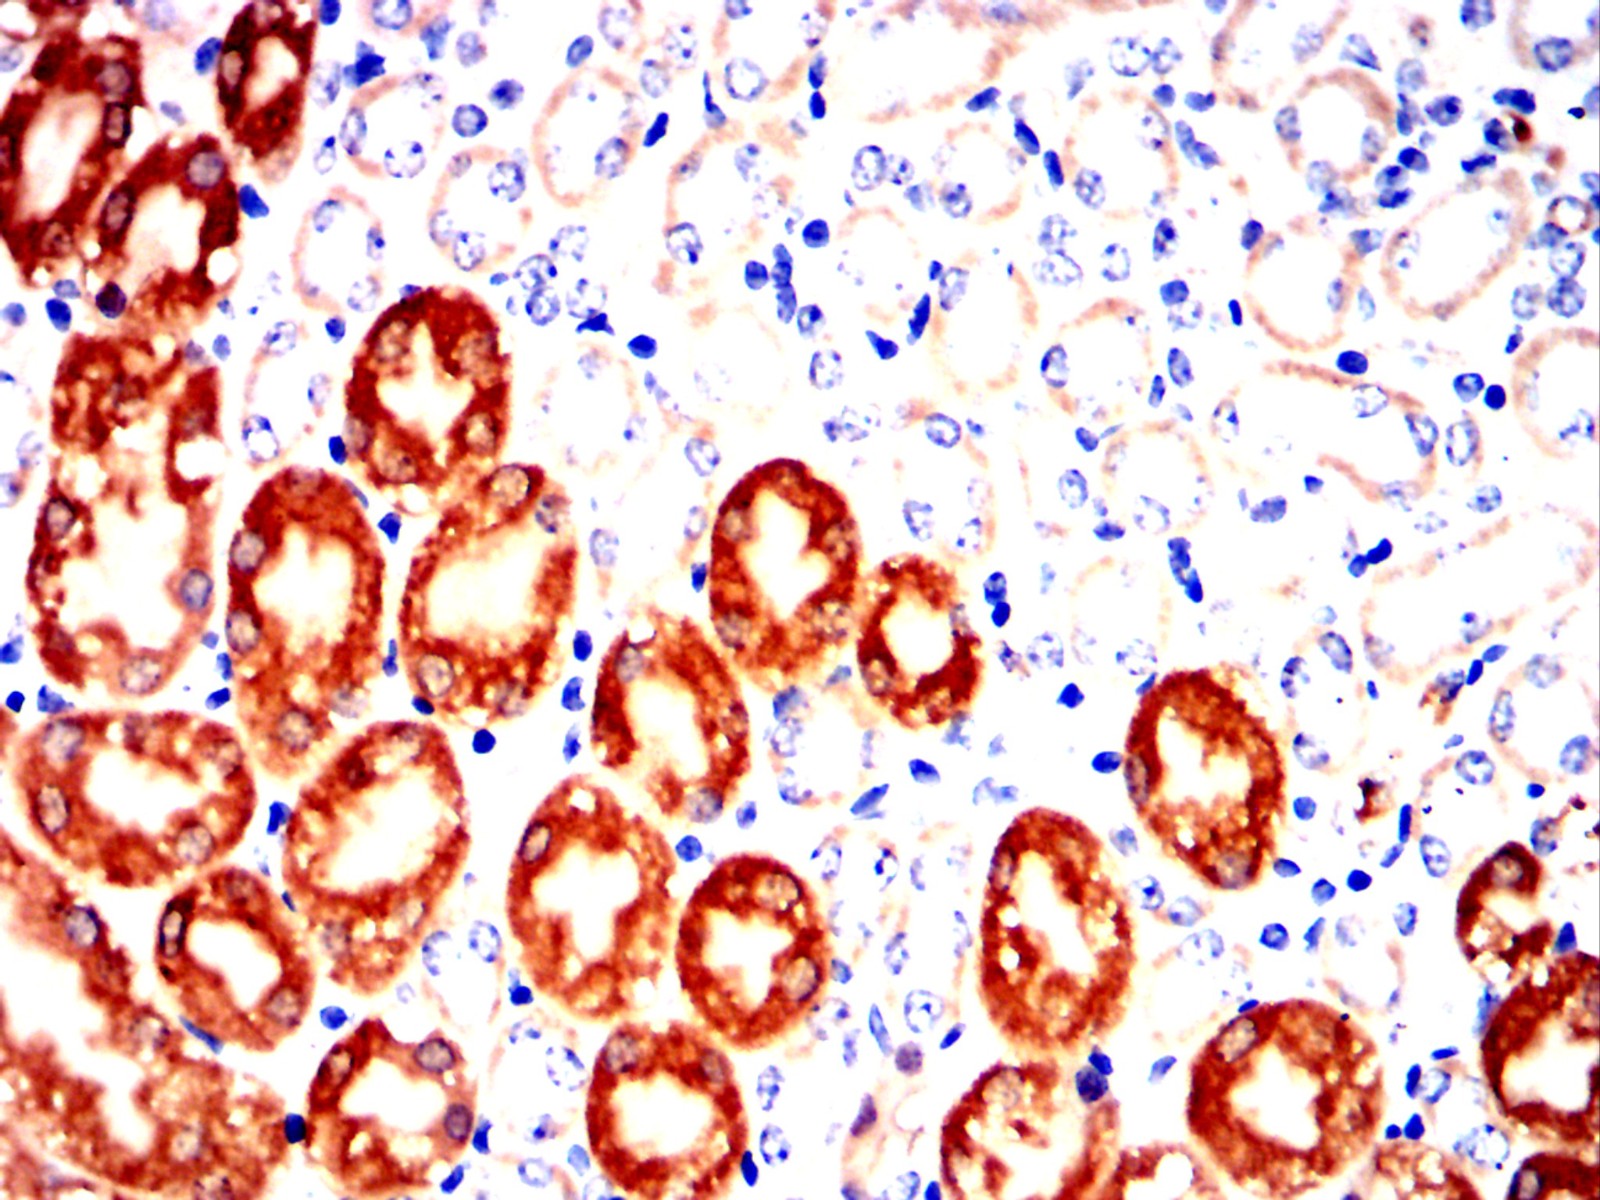

Immunohistochemical analysis of paraffin-embedded human pancreas tissues using CCL15 mouse mAb with DAB staining

Immunohistochemical analysis of paraffin-embedded Mouse kidney using CCL15 mouse mAb with DAB staining